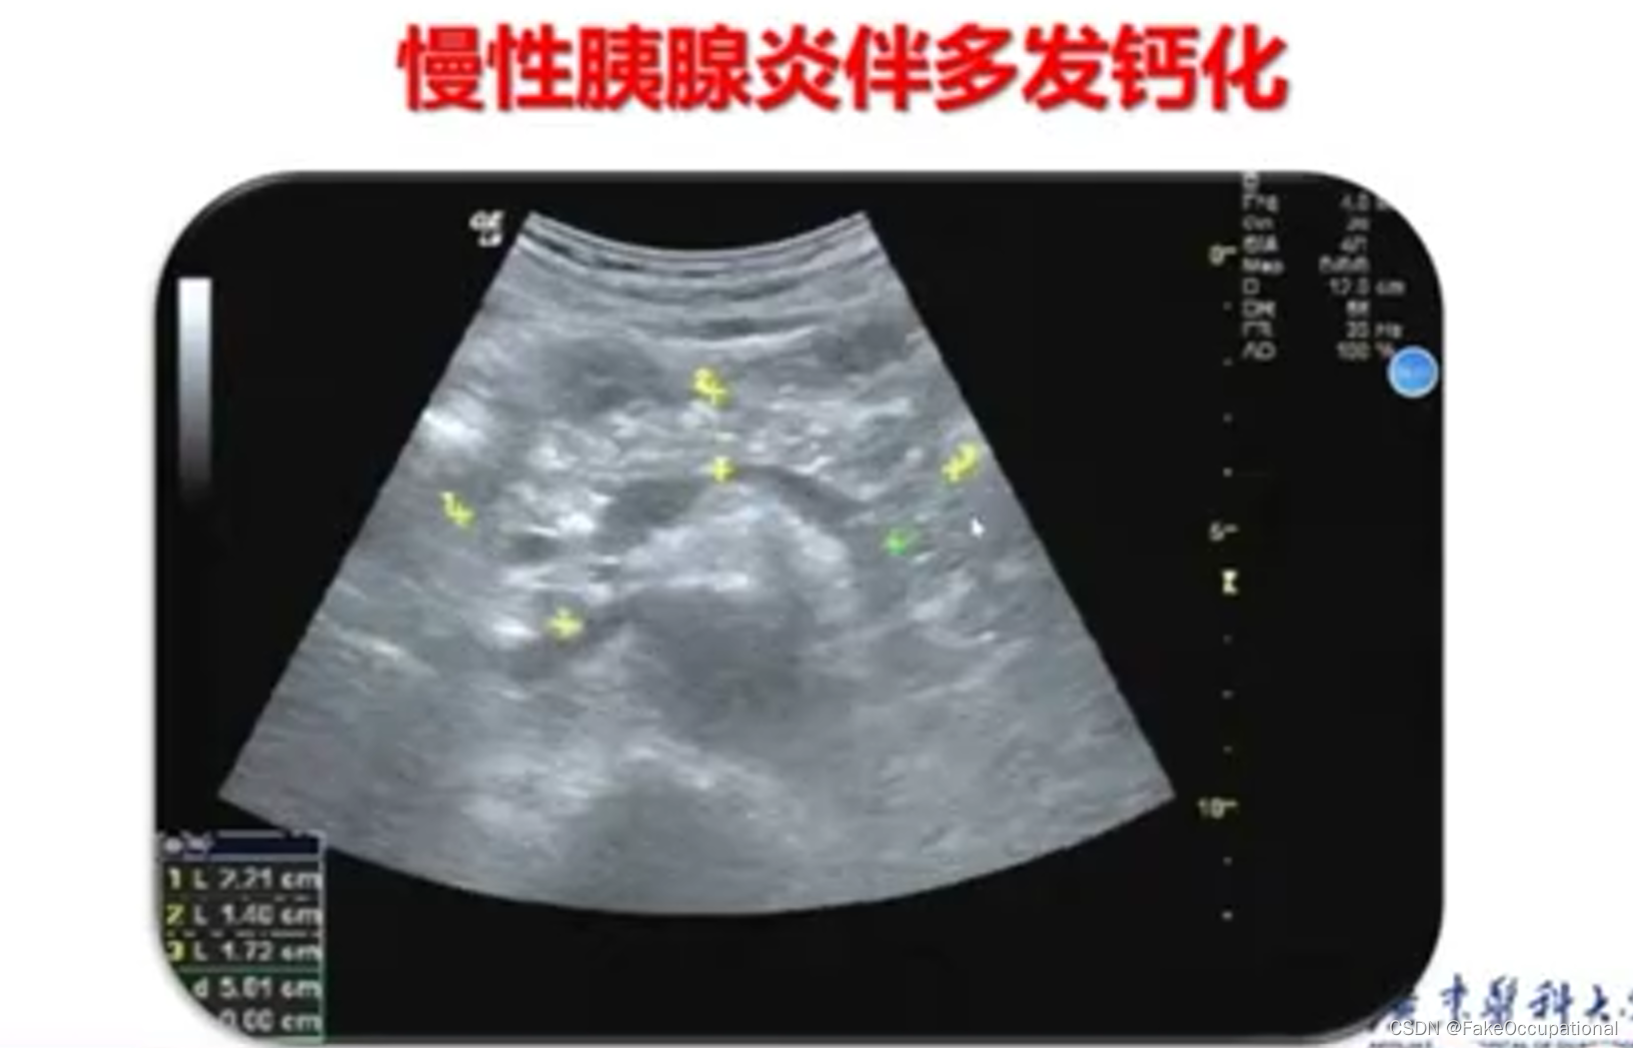

胰腺炎 — 急性胰腺炎、慢性胰腺炎